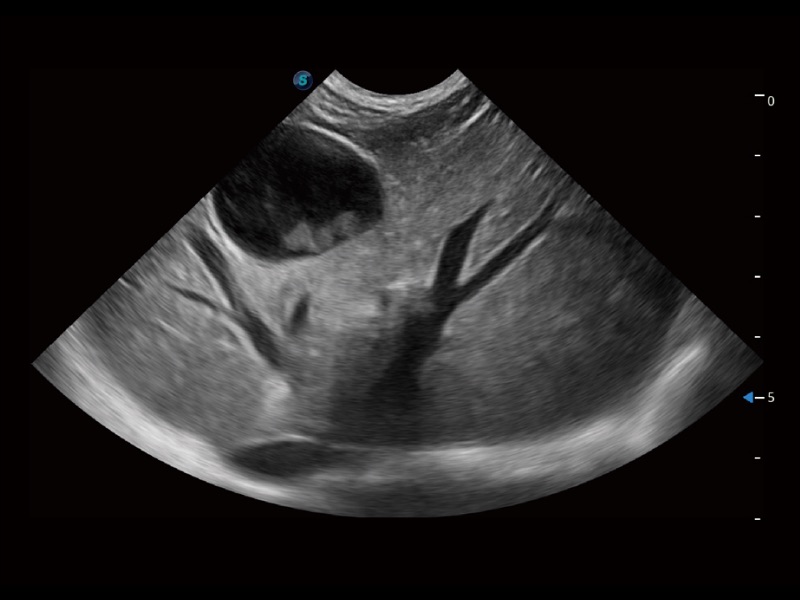

大型犬、馬科、農(nóng)場(chǎng)動(dòng)物及大型異寵動(dòng)物

通過(guò)創(chuàng)新的 Matrix E自適應(yīng)濾波器和超長(zhǎng)時(shí)間域算法,極大提升超低速微細(xì)血流的檢出能力,同時(shí)更精準(zhǔn)地濾除軟組織和噪聲信號(hào),為獸用醫(yī)生提供以往無(wú)法通過(guò)常規(guī)血流獲得的疾病診斷信息。

通過(guò)色彩血流和實(shí)時(shí)寬景相結(jié)合,可觀察到完整的靜脈或動(dòng)脈的血流,方便醫(yī)生檢查。實(shí)時(shí)掃查過(guò)程中,如有任何操作失誤也可以很容易地進(jìn)行回掃擦除,而不會(huì)中斷掃查。